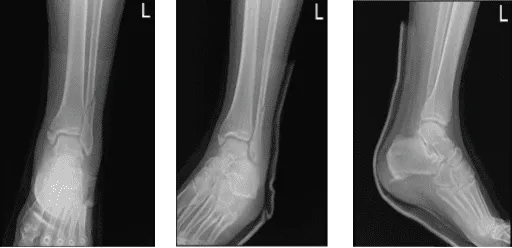

El paciente es un hombre de 60 años que fue visto en la consulta tras una caída desde el tejado. Tenía dolor e hinchazón en el tobillo izquierdo. Fue atendido por otro médico y le habló sobre opciones de tratamiento, incluyendo quirúrgico y no quirúrgico. Pero en ese momento rechazó la cirugía. Estaba viendo a otro profesional como segunda opinión.

Revisamos las radiografías y discutimos las opciones de tratamiento y las opciones quirúrgicas y no quirúrgicas. El paciente optó por el manejo quirúrgico. El paciente se ha recuperado recientemente del COVID y tiene antecedentes de coágulos sanguíneos, por los que tomó Eliquis, que ha dejado recientemente.

Radiografía completa del tobillo izquierdo 3 o más vistas